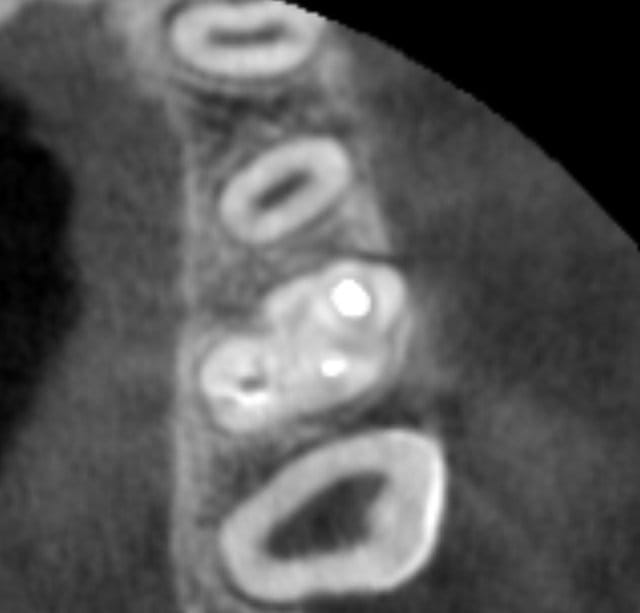

Et il y a bien un MV2 qui se reunit avec le MV1 ds le 13/ apical et a en plus une sortie propre.

c'est une autoroute toute droite, donc j'arrive à bien tout voir.

Hi, yup, c'etait juste pour avoir quelques plans de coupes en apical et en coronal par rapport a ton plan de coupe que tu nous a laissé ("avant arriere" voulait dire dans le déroulement des coupes!)) . Pour notre formation continue, c'est intéressant de faire l'analyse que tu as faite :fusion des deux canaux mésiaux au 1/3 apical! Tout le monde ne fait pas de la 3D endodontique , c'est pour notre connaissance.

Ok, donc 2 autres coupes axiales:

Mais au bout d'un moment la 3 d montre pas tout: tu peux ne pas voir une lumiere canalaire qui existe dans la dent.

+ l'artefact du gros cone de gutta

(j'ai mis 2 fois la meme : arrive pas à la retirer)